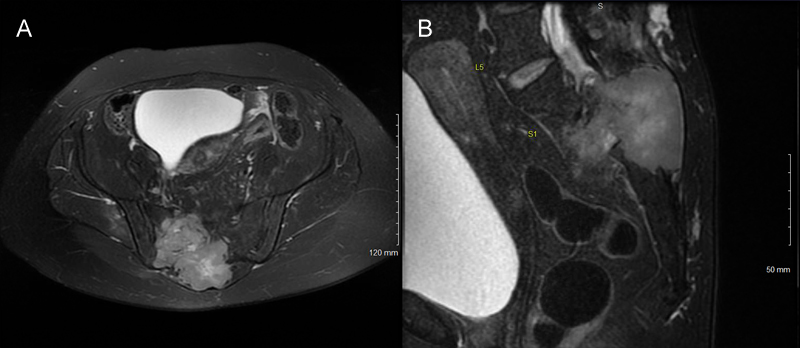

A 48-year-old female developed severe lower back and right buttock pain with right thigh numbness over a period of one year. She also reported difficulty urinating and defecating. Her past medical history included endometriosis, hypothyroidism, and multinodular goiter. On examination, she had saddle anesthesia and urinary retention. Computed tomography (CT) demonstrated a right sacral mass with posterior bony destruction. No local regional lymphadenopathy was appreciated. Magnetic resonance imaging (MRI) revealed a 7.8 x 8.6 cm heterogeneously enhancing mass with a large soft tissue component (Figure 1).

Figure 1: Tumor imaging. (A). Axial and (B). sagittal T2 MRI of the pelvis demonstrating an intermediate to brightly heterogeneously enhancing mass in the right sacrum and soft tissue with boney destruction.